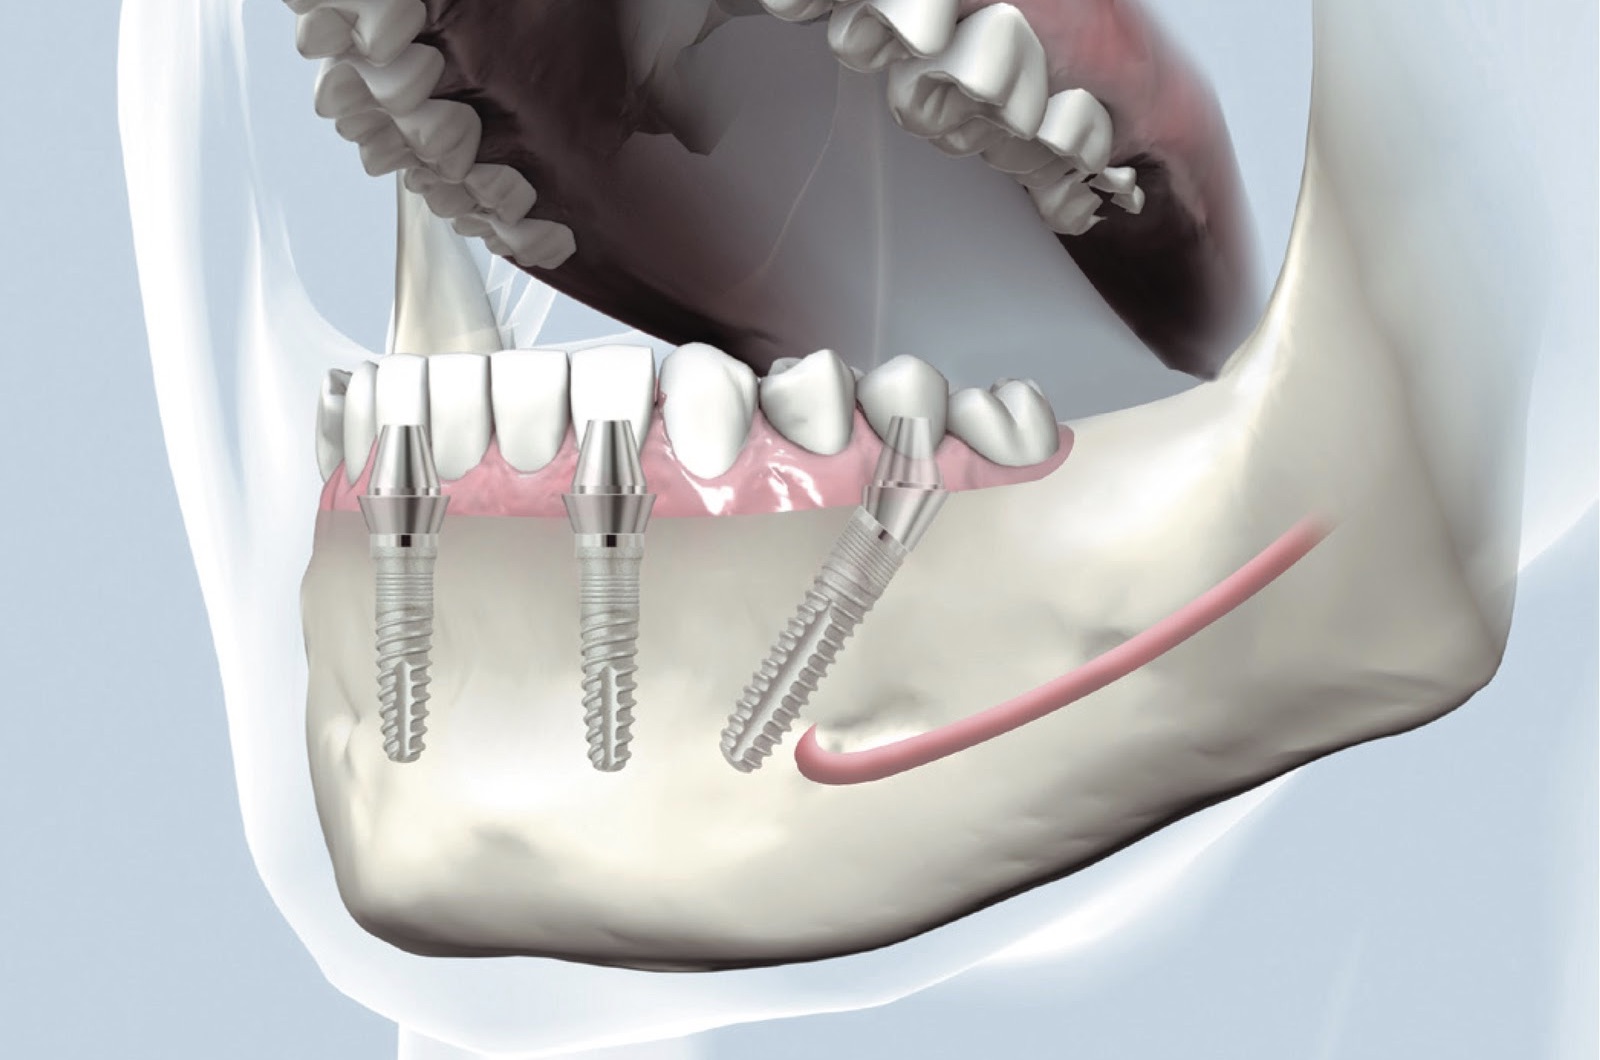

Современная стоматология: Железные зубные импланты